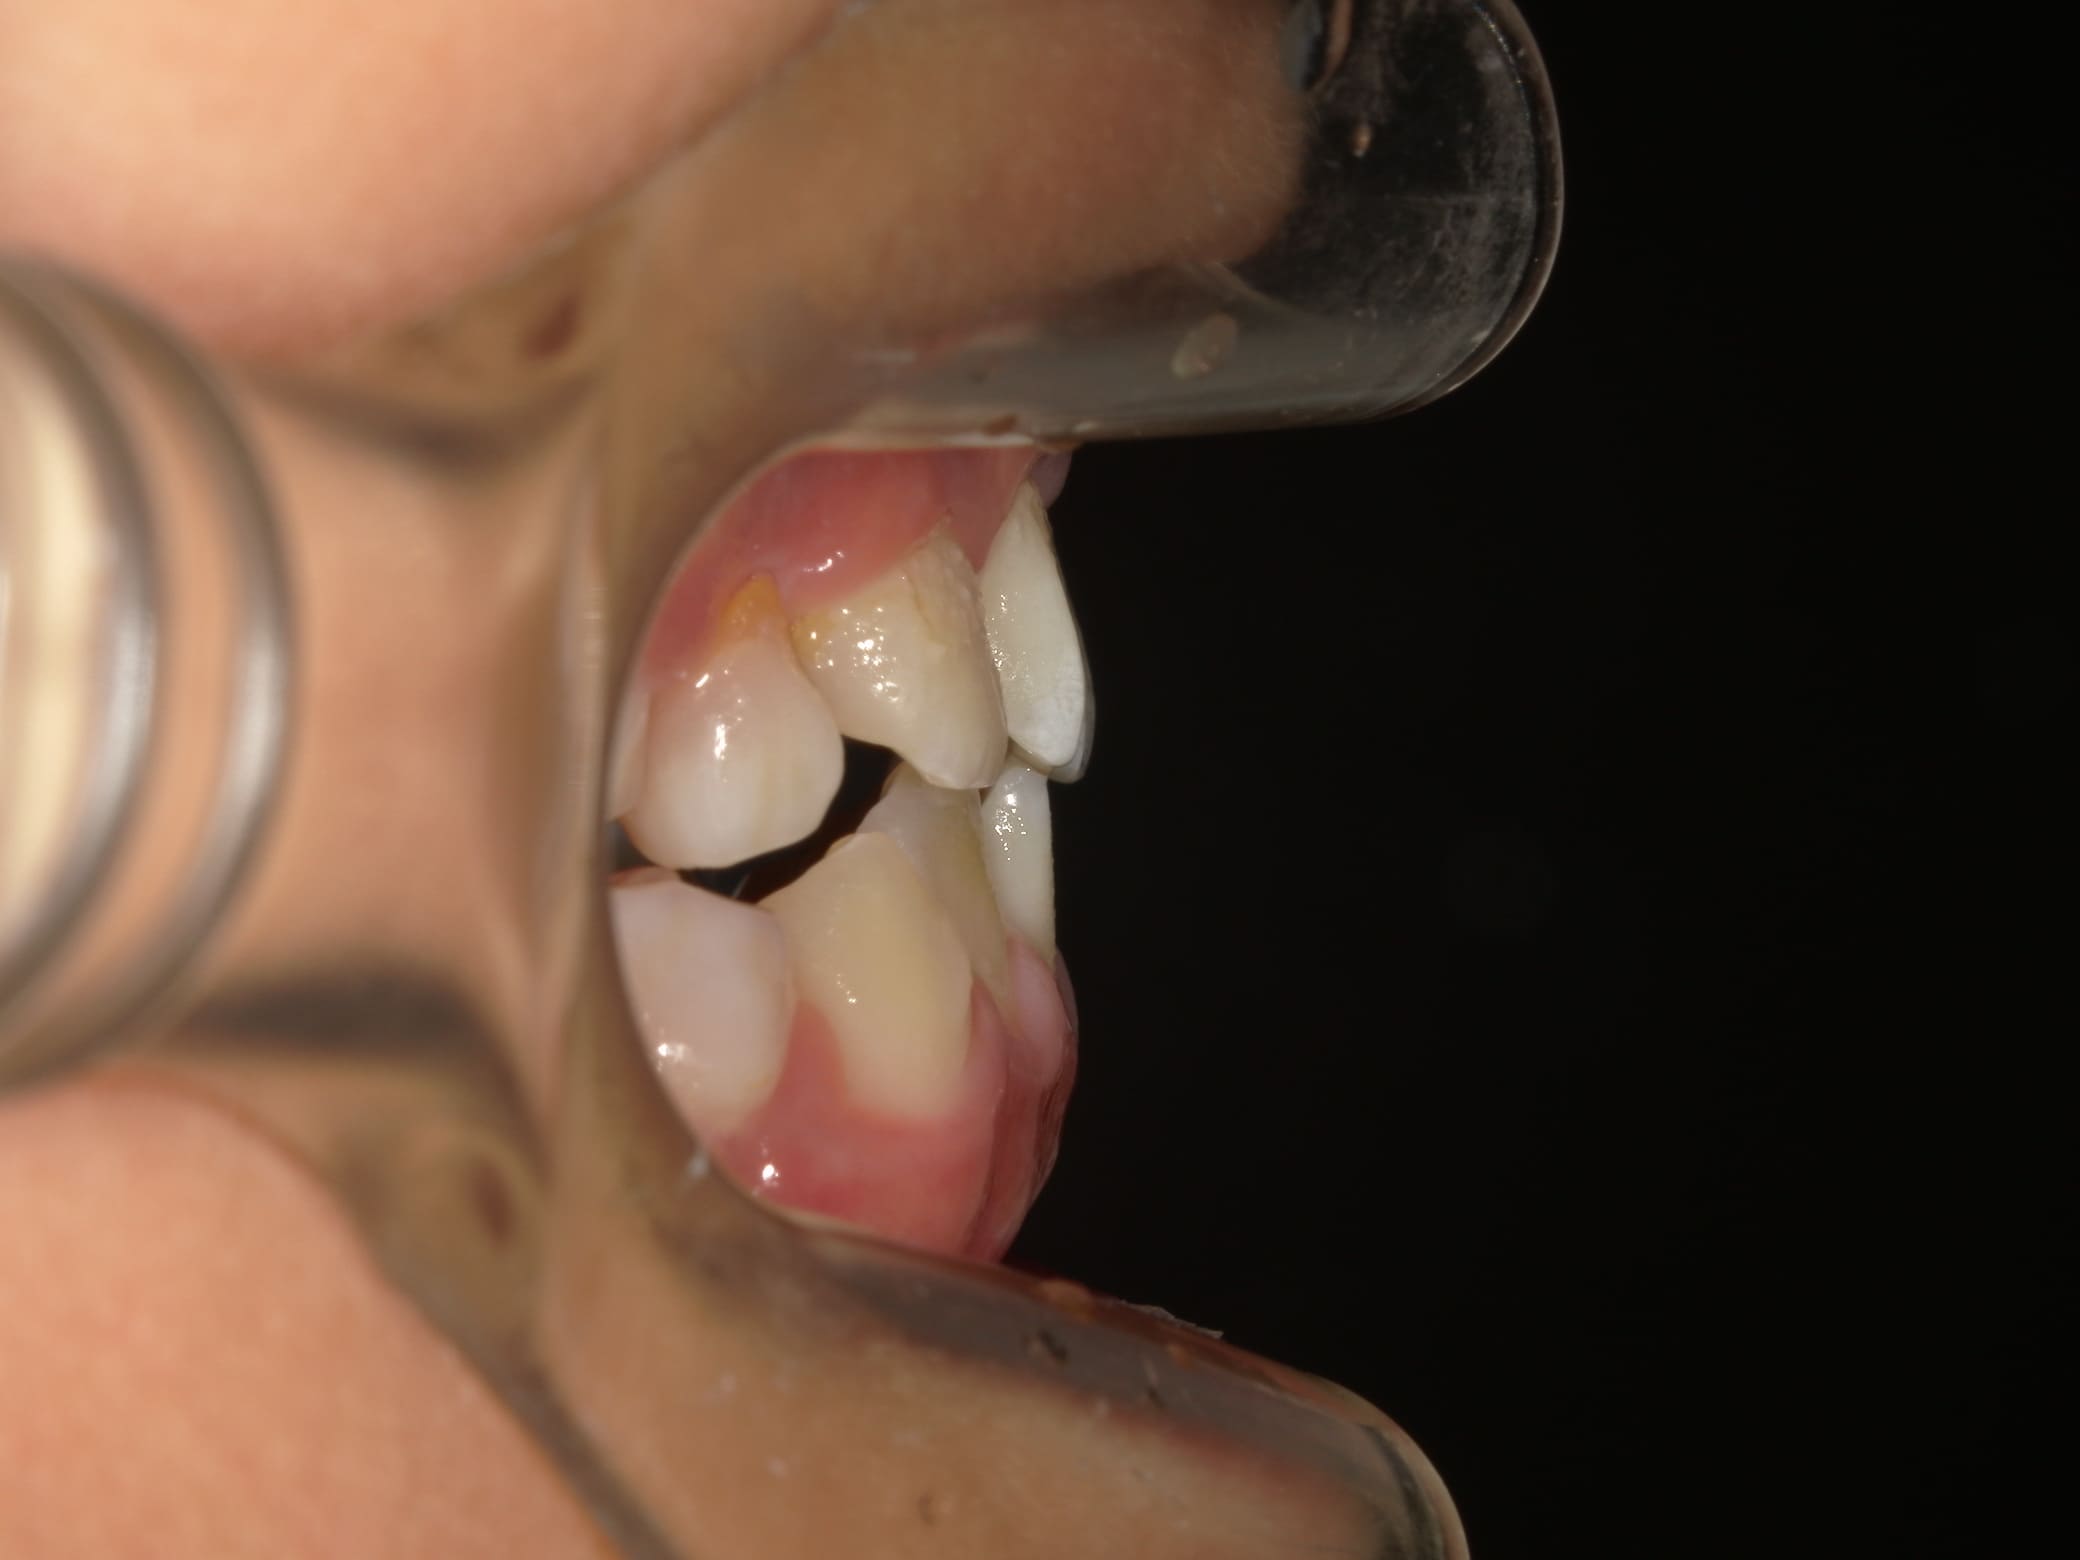

| 年齢・性別 | 8歳9ヶ月の女児 |

|---|---|

| 主訴 | 歯並びの乱れを気にされて来院された患者様です。将来的なスペース不足と歯のねじれ(翼状捻転)が懸念されました。 |

| 治療期間・回数 | 2年10ヶ月・19回 |

| 費用 | 430,000円(税別) |